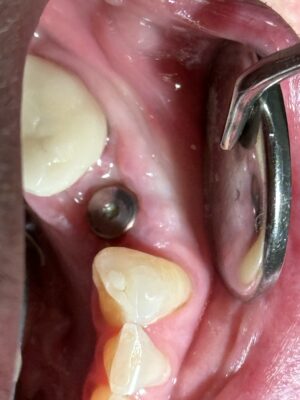

• Happy hump day. This was my win today. It always feels good to see an immediate implant placed two weeks ago healing this nicely 🙂